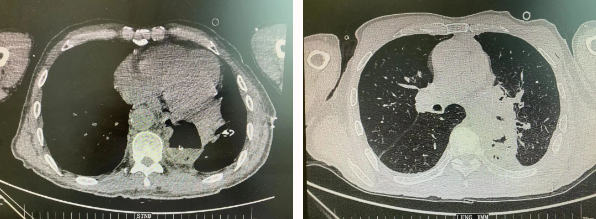

患者王某不幸同時患食管癌與左肺癌,病理類型系雙源發(fā)腫瘤,食管為鱗癌、肺為腺癌。食管癌和肺癌為胸外科最常見的疾病,但同時患兩種疾病,十分罕見。家屬輾轉(zhuǎn)多個醫(yī)院,得知李小飛院長擅長胸外科復(fù)雜手術(shù),慕名來西安國際醫(yī)學(xué)中心醫(yī)院。

經(jīng)過李小飛教授、李文海副教授、穆強副主任醫(yī)師團隊積極準(zhǔn)備,排除手術(shù)禁忌;經(jīng)過全科術(shù)前充分討論,大家認(rèn)為:如果分兩次進行手術(shù),另一種疾病勢必會受到影響,腫瘤可能進展。胸外科手術(shù)對呼吸循環(huán)影響較大,同期實施兩個手術(shù)更要小心謹(jǐn)慎。李小飛教授主持術(shù)前討論,設(shè)計合理手術(shù)方式,由于食管癌胸腔鏡手術(shù)為右側(cè)入路,但為兼顧左肺癌手術(shù),則采用傳統(tǒng)左開胸手術(shù)。

2022年4月25日,由李小飛教授主刀,同期行左側(cè)開胸:食管癌根治術(shù) 左肺癌根治術(shù),一次手術(shù)同時根治兩種惡性腫瘤疾病。經(jīng)過精細(xì)手術(shù)及術(shù)后管理,患者術(shù)后十天,恢復(fù)良好,進食良好,現(xiàn)已出院。